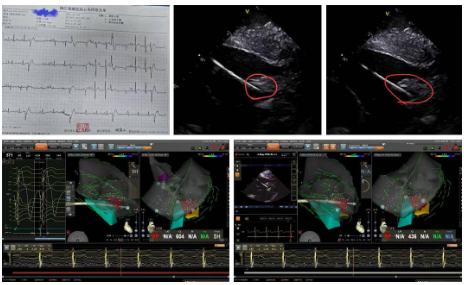

扬子晚报网12月25日讯(通讯员 刘柳 记者 万凌云 姜天圣)近日,镇江瑞康医院心内科在首席专家严金川教授精心组织下,成功完成两例心腔内超声(ICE)指导下左室乳头肌室早消融术,该技术是应用ICE精准指导结合三维标测系统,准确定位治疗乳头肌起源的室性早搏。

乳头肌起源的室性早搏因解剖结构特殊(如活动度大、导管贴靠困难),传统消融成功率较低。ICE技术通过将超声导管置入心脏,实时构建心腔三维图像,精准定位乳头肌并指导消融导管到位,提高成功率和安全性。

两例患者均为频发室性早搏,24动态心电图室早总数15000次左右,经多种药物治疗效果不佳,严重影响生活质量,遂慕名至镇江瑞康医院心内科就诊。结合患者体表心电图及腔内电生理标测结果,最终确定室早来源于左室后乳头肌内,消融术后动态心电图为极少数室性早搏,手术圆满成功。